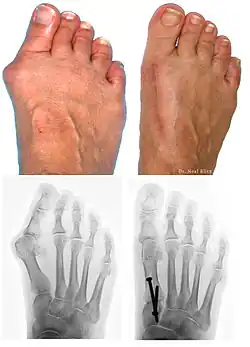

Surgery

Procedures are designed and chosen to correct a variety of pathologies that may be associated with the bunion. For instance, procedures may address some combination of:

- removing the abnormal bony enlargement of the first metatarsal,

- realigning the first metatarsal bone relative to the adjacent metatarsal bone,

- straightening the great toe relative to the first metatarsal and adjacent toes,

- realigning the cartilaginous surfaces of the great toe joint,

- addressing arthritic changes associated with the great toe joint,

- repositioning the sesamoid bones beneath the first metatarsal bone,

- shortening, lengthening, raising, or lowering the first metatarsal bone,

- correcting any abnormal bowing or misalignment within the great toe,

- connecting two parallel long bones side by side by syndesmosis procedure

At present there are many different bunion surgeries for different effects. The age, health, lifestyle and activity level of the patient may also play a role in the choice of procedure.

Traditional bunion surgery can be performed under local, spinal or general anesthetic. A person who has undergone bunion surgery can expect a 6- to 8-week recovery period during which crutches are usually required to aid mobility. An orthopedic cast is much less common today as newer, more stable procedures and better forms of fixation (stabilizing the bone with screws and other hardware) are used. Hardware may even include absorbable pins that perform their function and are then broken down by the body over the course of months. After recovery long term stiffness or limited range of motion may occur in some patients. Visible or limited scarring may also occur for patients.